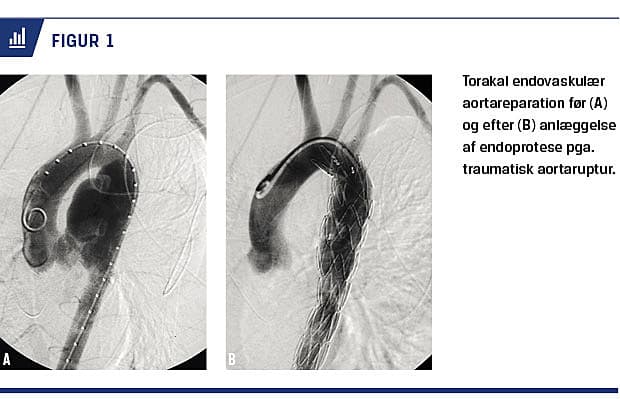

VENØSE INTERVENTIONER

Perkutan sklerosering er et behandlingstilbud til patienter med venøse og lymfatiske malformationer og intravaskulær okklusion er et tilbud ved venøs insufficiens som f.eks. varicer eller pelvic congestion syndrome. Embolisering af pulmonale arteriovenøse malformationer har helt erstattet kirurgi (Figur 4).